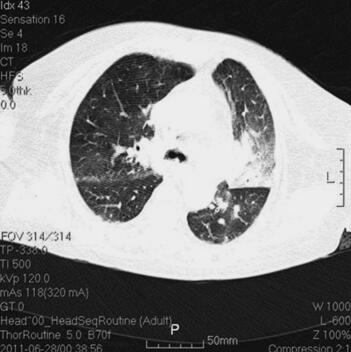

诊治经过:入院后留置右锁骨下深静脉导管,监测CVP。患者血压逐渐平稳,停用多巴胺。继续机械通气,头孢哌酮-舒巴坦钠针剂及阿奇霉素针剂联合抗感染,甲泼尼龙及多索茶碱解痉平喘,改善微循环,化痰等对症支持治疗。并予肠内营养,胰岛素微泵控制血糖。复查胸部CT(7月4日)(图2),感染较前明显吸收;复查(7月4日)CRP 10mg/L,PCT 0.22ng/ml。

图2 胸部CT(7月4日),感染较前明显吸收